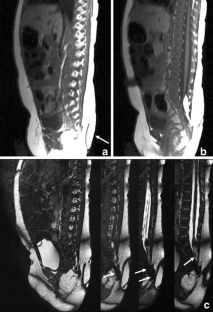

We present a female baby with a human tail associated with congenital dermal sinus (CDS) at the caudal site of the tail. Magnetic resonance (MR) images with constructive interference in steady-state (CISS) sequencing clearly demonstrated a lumbosacral lipoma of caudal type, contiguous with the dermal sinus tract and not with the human tail. At 3 months old, the tail was surgically removed. The dermal sinus tract and contiguous lipoma were also resected, and untethering of the spinal cord was performed. Although both the human tail and CDS are frequently associated with spina bifida occulta, coexistence of the tail and CDS is exceedingly rare. CISS-MRI is useful for demonstrating the precise anatomical relationship between these complicated pathologies.

Fig. 2